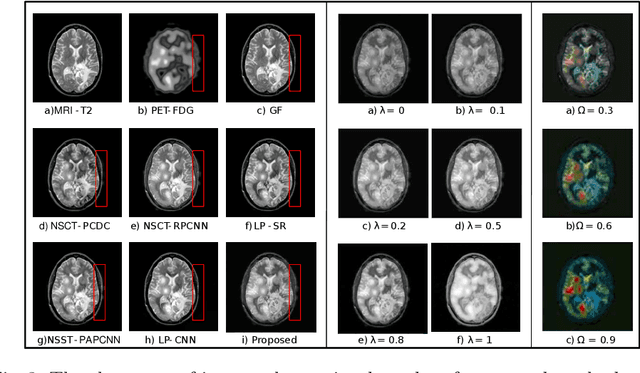

Abstract:Multimodal medical image fusion helps in combining contrasting features from two or more input imaging modalities to represent fused information in a single image. One of the pivotal clinical applications of medical image fusion is the merging of anatomical and functional modalities for fast diagnosis of malignant tissues. In this paper, we present a novel end-to-end unsupervised learning-based Convolutional Neural Network (CNN) for fusing the high and low frequency components of MRI-PET grayscale image pairs, publicly available at ADNI, by exploiting Structural Similarity Index (SSIM) as the loss function during training. We then apply color coding for the visualization of the fused image by quantifying the contribution of each input image in terms of the partial derivatives of the fused image. We find that our fusion and visualization approach results in better visual perception of the fused image, while also comparing favorably to previous methods when applying various quantitative assessment metrics.